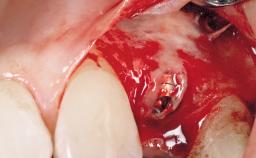

A 42-year-old female patient was referred to our clinic at the School of Dentistry of the University of São Paulo in November 2004, presenting a deficient restoration in the upper left central incisor. The clinical examination revealed no gingival retraction or any signs of gingival inflammation and, therefore, previous periodontal treatment was not considered. The patient presented a high lip line at full smile and a thin tissue biotype. This combination characterized a high-risk situation from an anatomic point of view, which required careful preoperative planning and cautious surgical execution.

Placement Protocol Immediate implant placement

Socket Morphology Single-root socket

Socket Integrity Sufficient, with intact bone walls